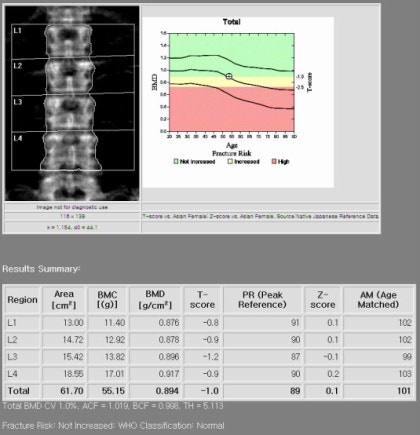

골밀도가 조금씩 감소하면서 뼈는 약해지고, 작은 자극에도 뼈가 부러지는 경우가 많습니다. 폐경기, 저체중, 운동 부족, 칼슘 부족 등이 골다공증을 유발할 수 있다고 합니다. 골다공증을 효과적으로 관리하기 위해서는 골다공증 수치를 올바르게 읽는 방법을 알아두는 것이 좋습니다.

골다공증 수치*T-점수로 진단 골밀도 정상 수치: T-값 -1 이상 골밀도 비정상 수치(골감소증): -1~2.5 이상 골밀도 수치(골다공증): -2.5 이하 어머니도 골다공증 수치 정상적인 골다공증 수치가 범위보다 낮게 나와서 걱정이 많았고, 골다공증 수치를 높이기 위해 많은 노력을 기울였습니다. 골다공증은 뼈의 양이나 질이 떨어져 근력이 약해지는 질환으로, 일상생활에서 일반적인 충격에도 쉽게 부러지는 질환이다. 그래서 골다공증 수치를 높이기 위해 낮에 햇빛을 많이 받으면서 골다공증 수치를 효과적으로 관리할 수 있는 방법을 찾다가 우리 농장에서 나온 식용 달팽이를 달여서 계속 먹을 수 있게 되었습니다. 골다공증 수치를 효과적으로 관리하는 방법은 무엇입니까? 식용 달팽이 섭취하기 식용 달팽이는 골다공증 예방과 뼈 건강에 탁월한 식품으로 알려져 있습니다. 흔한 달팽이가 아닌 식용 달팽이로 우리나라에서는 약용으로 많이 이용되고 있습니다. 골다공증 예방 및 효과적인 관리 칼슘 섭취가 필요하다는 사실 알고 계셨나요? 식용 달팽이에는 칼슘과 단백질이 다량 함유되어 있어 골다공증으로 고통받는 분들뿐만 아니라, 근력을 보충하고 뼈 건강을 지켜주는 탁월한 식품 중 하나이며, 운동선수와 노인에게도 마찬가지입니다. 또한 달팽이에 다량 함유되어 있는 콘드로이틴이 가장 특징적인 성분이다. 관절의 27~43%를 구성하는 성분으로 인대의 탄력과 유연성을 유지시켜 골다공증 예방 및 관리에 도움을 줍니다. 이 때문에 갱년기 여성을 찾는 여성들이 많다. 단백질이 많이 함유되어 우수한 건강식품으로 꼽히는 식용 달팽이는 칼슘이 풍부하고 지방이 적어 관절염에 탁월한 고단백 식품이다. 우리나라에서는 골다공증에 좋은 음식으로 알려져 있으며, 뼈를 건강하고 튼튼하게 해주는 음식으로 유명합니다. 나이가 들수록 뼈 건강에 신경을 많이 쓰는 편이라 달팽이를 꾸준히 섭취하다 보니 골다공증 수치가 거의 정상 수준으로 유지되고 있습니다. 보내드립니다. 이때에도 골다공증에 도움이 되는 몇 가지 약초를 첨가한 달임이라 저희 농장 달팽이추출물을 꾸준히 찾아주시는 이유가 아닐까 싶습니다. 제가 모아서 달여먹는 약재 몇 가지만 소개하겠습니다. 첫 번째는 홍화씨입니다. 잇꽃씨는 골다공증, 퇴행성관절염, 척추질환, 관절질환 등에 효능이 입증되어 오랫동안 사용해 온 약재 중 하나이다. 두 번째는 오가피입니다. 오가피는 체내 뼈와 근육 세포를 생성하고, 힘줄과 뼈를 튼튼하게 하여 근육을 강화시키며, 칼슘 흡수를 도와 골다공증을 예방 및 개선시키는 것으로 알려져 있습니다. 그 외에도 많은 약초가 있습니다. 여기에 사용되는 허브는 직접 재배하거나 자연에서 채취한 허브를 저온 수조에 15시간 정도 삶아낸 것입니다. 골다공증 수준의 효과적인 관리1. 칼슘과 비타민D의 흡수 장에서 칼슘의 섭취를 늘리고 신장에서 배설을 줄여 체내 칼슘을 보존합니다.2. 운동 체중 부하 운동, 점핑, 호핑 등이 뼈 건강에 도움이 된다고 합니다.3. 과도한 음주와 흡연은 뼈의 형성을 감소시키고 칼슘의 흡수를 감소시킵니다.4. 여성의 폐경 후 에스트로겐은 골밀도를 유지하는 역할을 하지만, 폐경기 동안 에스트로겐이 감소하면 골다공증이 발생할 수 있습니다. 유전적 요인 유전적 소인으로 인해 최대골량의 형성이 잘 되지 않는다고 합니다.6. 아울러… 카페인 섭취를 제한하고, 콩과 콩제품을 충분히 섭취하고, 콩 이소플라본을 섭취하는 것이 골다공증 예방에 도움이 된다고 합니다. 식용 달팽이는 누군가에게는 생소할 수도 있지만, 뼈 건강에 매우 도움이 되고 신체 회복에도 탁월합니다. 음식이라는 사실을 기억하시고, 뼈 건강과 골다공증 예방 및 관리를 위해 미리 드셔보시는 건 어떨까요?